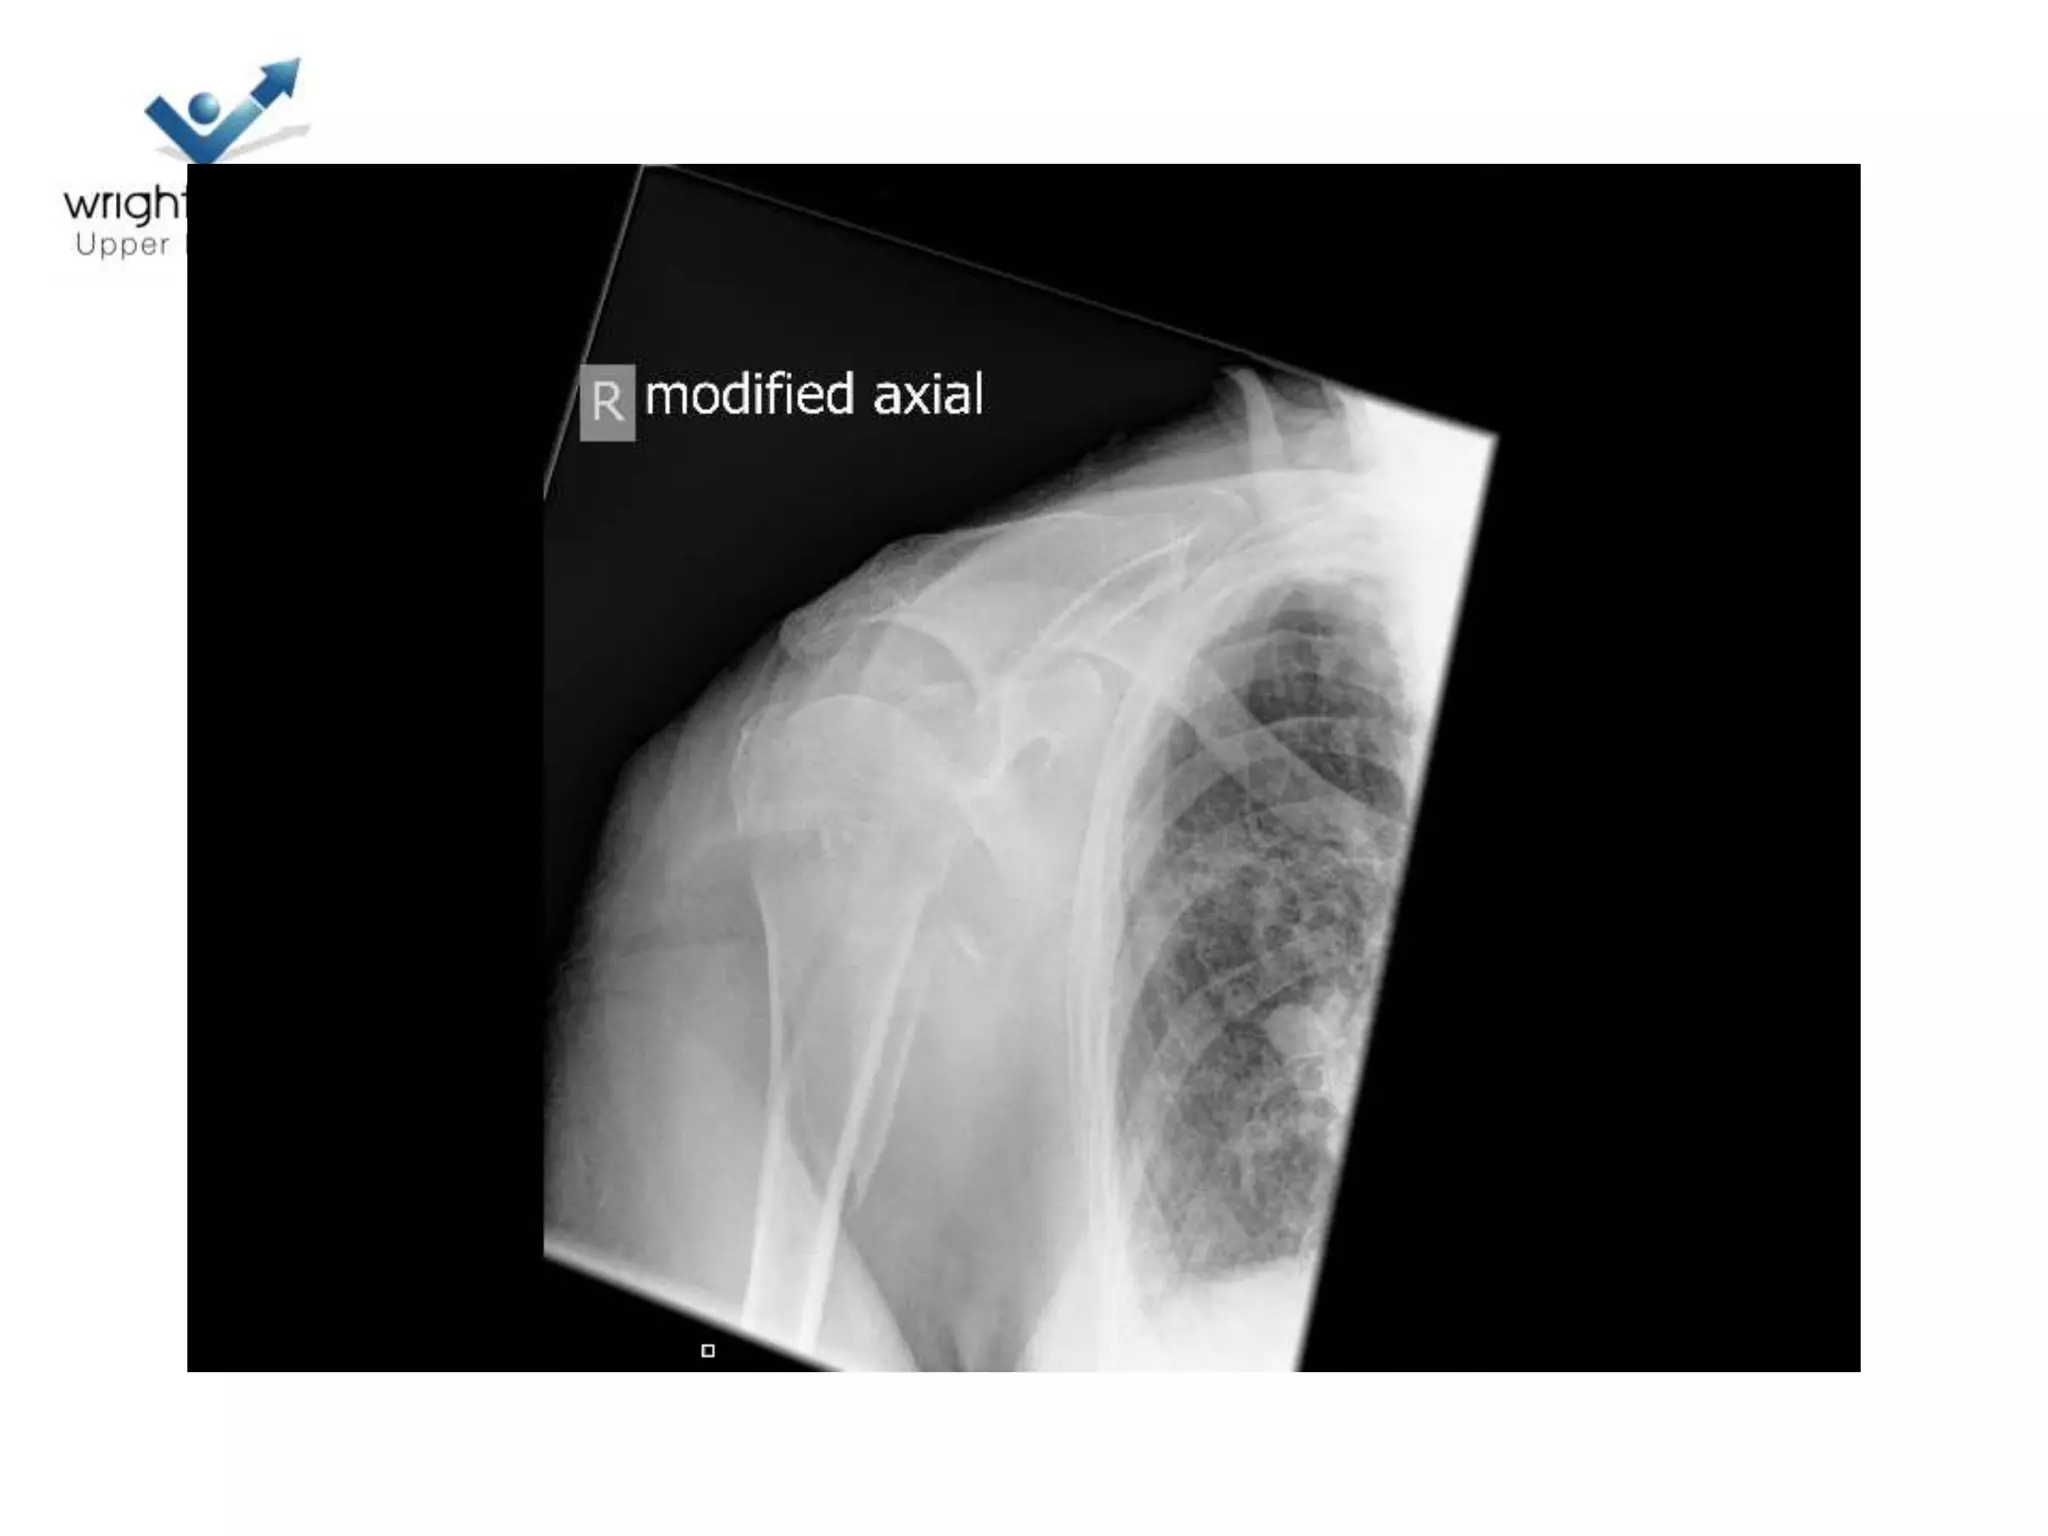

Head Ischaemia

1. Posteromedial Calcar

Predictor no 2.Medial Hinge

Medial Hinge